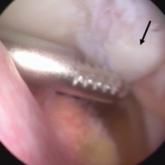

ArticleCorrect Positioning of the Medial Patellofemoral Ligament: Troubleshooting in the Operating RoomAuthor:M. Tyrrell Burrus, MDPublish date: March 1, 2017Medial patellofemoral ligament (MPFL) reconstruction is often required after failed nonoperative management of lateral patellar instability. It is ...Read More